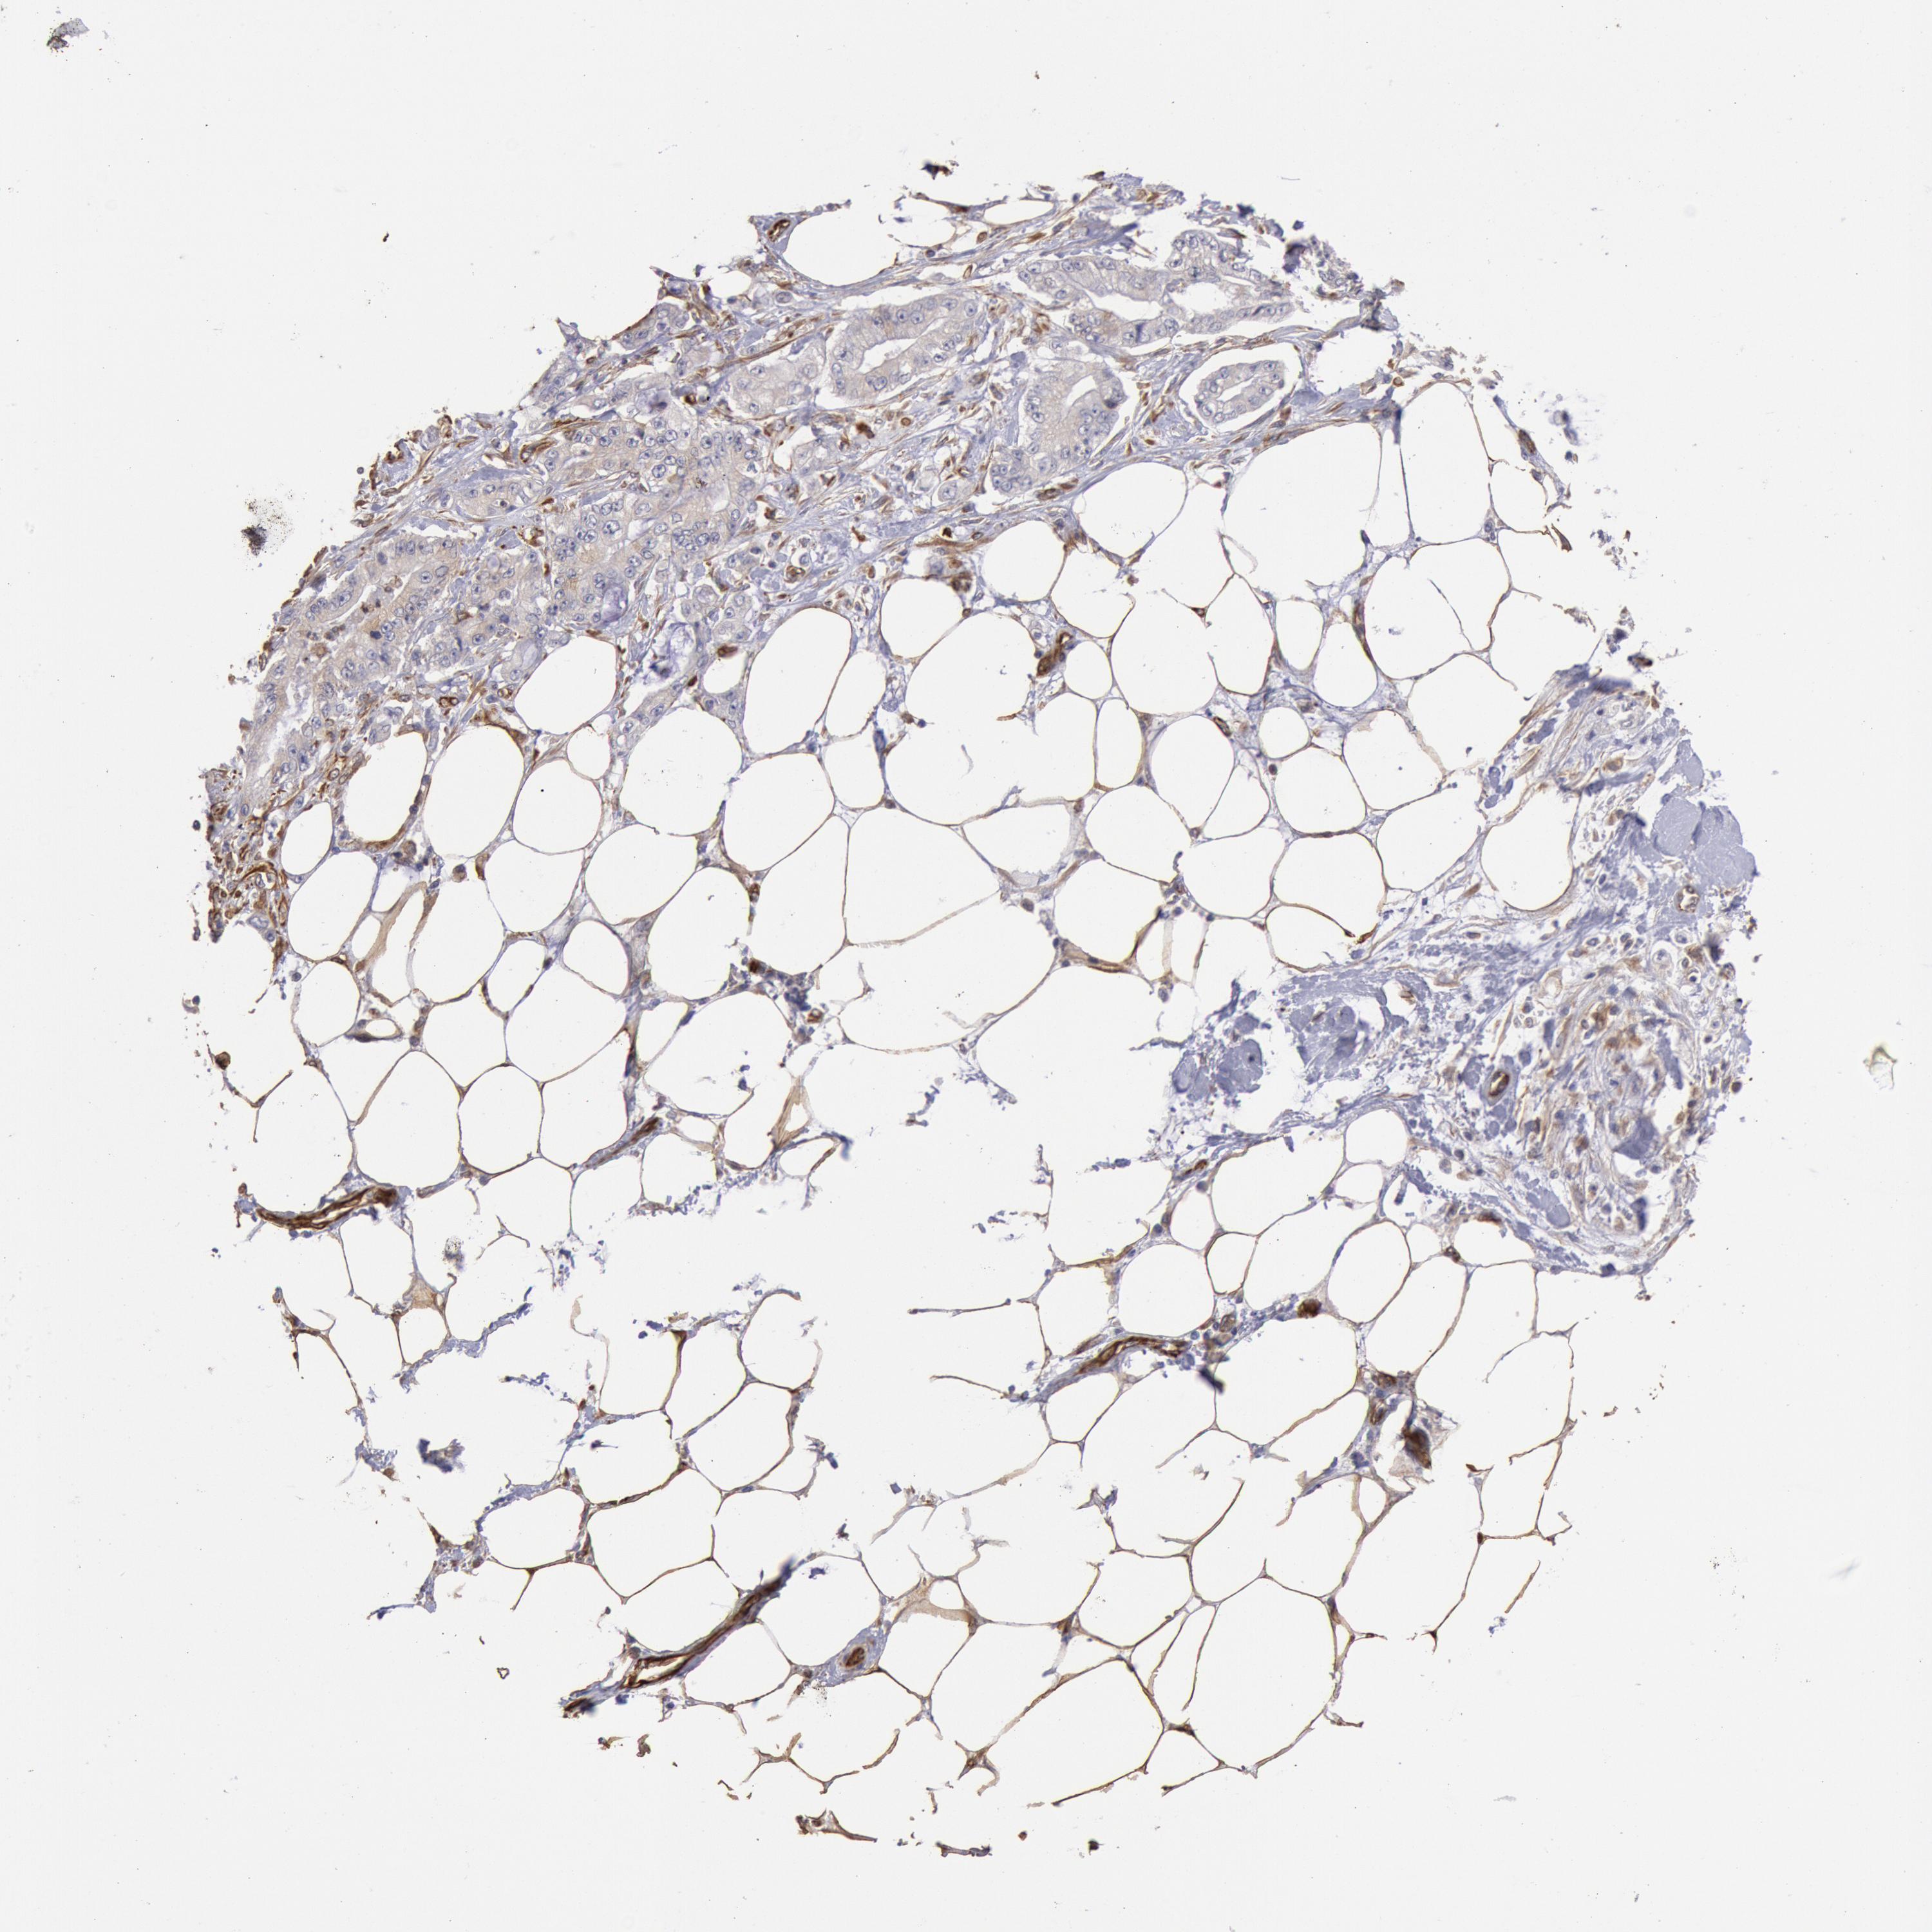

PANCREATIC CANCER - Protein expressioni

A mouse-over function shows sample information and annotation data. Click on an image to view it in a full screen mode. Samples can be filtered based on level of antibody staining by selecting one or several of the following categories: high, medium, low and not detected. The assay and annotation is described here.

Note that samples used for immunohistochemistry by the Human Protein Atlas do not correspond to samples in the TCGA dataset.

Antibody stainingi

Antibody staining in the annotated cell types in the current human tissue is reported as not detected, low, medium, or high, based on conventional immunohistochemistry profiling in selected tissues. This score is based on the combination of the staining intensity and fraction of stained cells.

Each image is clickable and will lead to virtual microscopy that enables deeper exploration of all samples and also displays staining intensity scores, fraction scores and subcellular localization as well as patient and tissue information for each sample.

Antibody HPA001202

Staining

High

Medium

Low

Not detected

Intensity

Strong

Moderate

Weak

Negative

Quantity

>75%

75%-25%

<25%

None

Location

Nuclear

Cytoplasmic/membranous

Cytoplasmic/membranous,nuclear

Adenocarcinoma, NOS